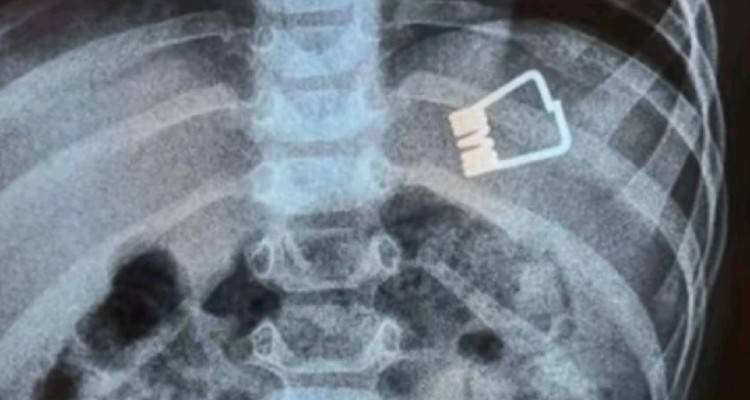

Μεγάλη περιπέτεια πέρασαν ένα αγοράκι δυο ετών και η οικογένειά του στη Λήμνο, όταν το παιδί κατάπιε ένα μανταλάκι και χρειάστηκε να διακομιστεί στο Ιπποκράτειο Νοσοκομείο στη Θεσσαλονίκη. Εκεί, οι γιατροί κατάφεραν να βγάλουν το μανταλάκι από τον οργανισμό του παιδιού χωρίς χειρουργική επέμβαση, αλλά με τη βοήθεια ενός ενδοσκοπίου τελευταίας γενιάς.

Σύμφωνα με το ρεπορτάζ της ΕΡΤ, το παιδί κατάπιε το μανταλάκι στο σπίτι του και στη συνέχεια μεταφέρθηκε με Super Puma από τη Λήμνο στη Θεσσαλονίκη, όπου το ανέλαβαν οι παιδίατροι.

«Όταν το παιδί έφτασε εδώ αμέσως κινητοποιηθήκαμε, ενημερώσαμε τους αναισθησιολόγους, είχαμε έτοιμο το χειρουργικό κρεβάτι. Το παιδί έπρεπε είναι νηστικό 6 με 8 ώρες και προβήκαμε στην αφαίρεση ενδοσκοπικά του ξένου σώματος», δήλωσε ο Ιωάννης Ξηνίας, αναπληρωτής καθηγητής Παιδιατρικής Γαστρεντερολογίας.

Το παιδί επέστρεψε στη Λήμνο και είναι καλά στην υγεία του.